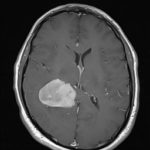

Cette masse peut entrainer notamment :

- Une irritation du cerveau qui se manifeste par une épilepsie

- Une compression voire destruction d’une partie du cerveau causant un affaiblissement ou une perte d’une fonction du cerveau

- Une augmentation de la pression à l’intérieur du crâne (espace inextensible à l’intérieur duquel vient s’ajouter le volume de la tumeur), ce qui va se manifester initialement par des maux de tête d’aggravation progressive qui vont s’associer à des nausées, des vomissements, des troubles visuels… Cet état peut aboutir à la perte de la vue dans les formes d’évolution lente et au décès dans les formes d’évolution rapide.